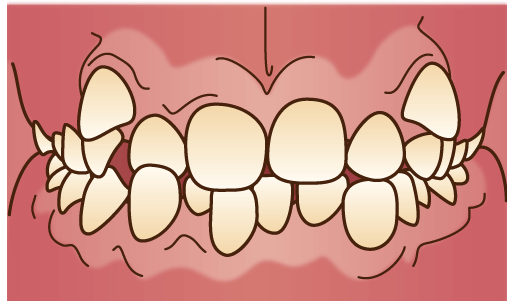

叢生(そうせい)

代表的なものが「八重歯」です。歯がでこぼことズレていたり、重なって生えている状態です。顎が小さいために歯が並ぶスペースが足りない場合や、顎に対して歯が大きすぎる場合に起こりやすくなります。

代表的なものが「八重歯」です。歯がでこぼことズレていたり、重なって生えている状態です。顎が小さいために歯が並ぶスペースが足りない場合や、顎に対して歯が大きすぎる場合に起こりやすくなります。